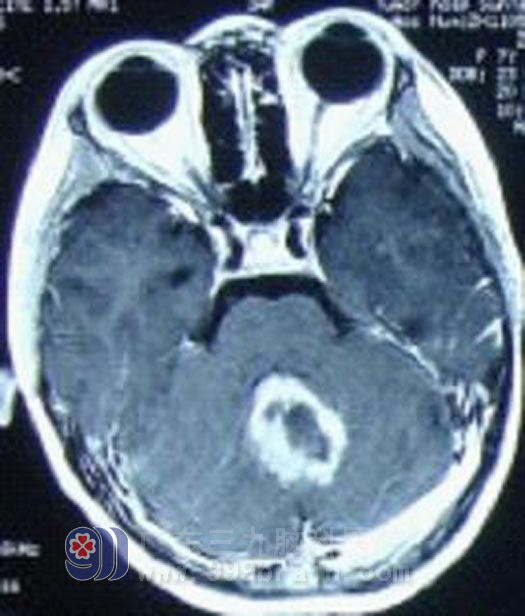

7岁的扬扬是一个快乐的小女孩,今年3月开始无诱因出现恶心呕吐情况,开始约每天一次,呈喷射状,开始父母未引起重视,以为只是普通的感冒,未进行积极地治疗,渐渐呕吐频繁加重,4月到当地儿童医院就诊,诊断为地中海贫血,予对症治疗后呕吐症状无好转。即至广州某肿瘤医院就诊,头颅MR显示为小脑蚓部囊性病变,专家考虑为毛细胞型星形细胞瘤,不排除髓母细胞瘤。经过完善相关检查后5月24日行占位切除术,术后病理显示为髓母细胞瘤。手术后扬扬恶性呕吐症状消失,出现行走步态欠稳。在家康复一段时间后,6月24日我院就诊,扬扬一般情况良好,经过详细计划后即开始行全中枢放疗,放疗后复查头颅MR示术区边缘强化明显减退,再行术区适形加量放疗。http://www.999brain.com/

治疗前